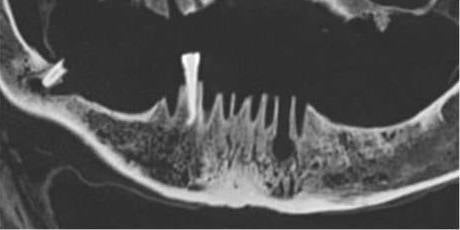

Muestra de la mandíbula con el colmillo inferior derecho y lesiones características de los abscesos odontógenosUCM / Archimadrid

Compartir

Los investigadores no han hallado signos de violencia o traumatismos que puedan esclarecer el motivo de la muerte, pero sí han evidenciado enfermedades infecciosas en los huesos maxilares que podrían haber desembocado en una sepsis, posible causa del fallecimiento del santo.